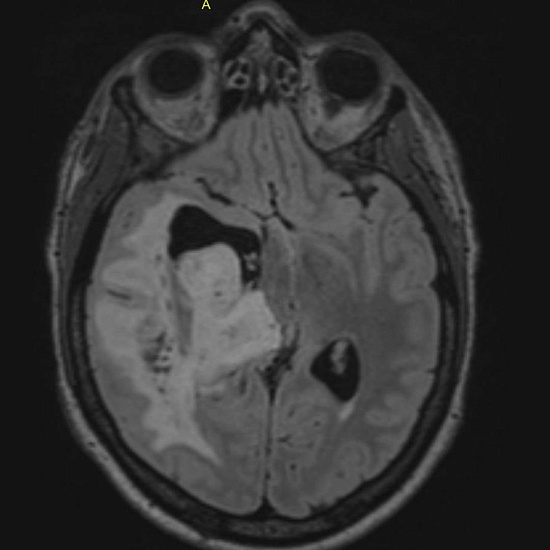

При проведении МРТ головного мозга выявлена опухоль правой височно-теменной области с переходом на островок, вовлечением базальных ядер справа и мозолистого тела с выраженным перифокальным отеком с дислокацией срединных структур мозга влево, компрессией правых бокового и третьего желудочков, среднего мозга.

При введении контрастного препарата визуализировался участок интенсивного кольцевидного накопления по периферии кистозного компонента опухоли.